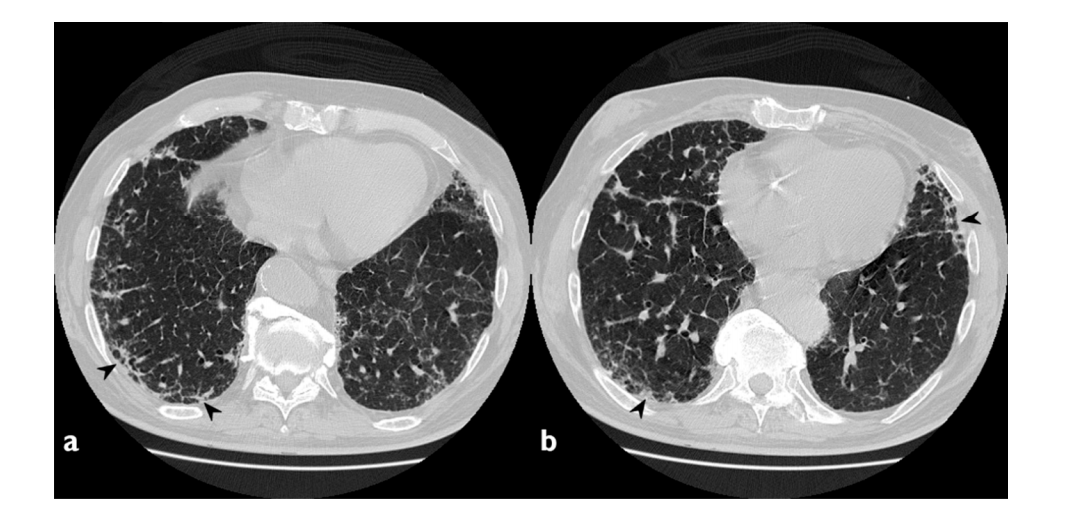

①肺实变磨玻璃密度影;②小叶周围阴影;③环礁征;④结节或肿块;⑤小叶间隔增厚;⑥束状或条带阴影;⑦进行性纤维化。

图片

隐源性机化性肺炎主要的影像学表现

图片来源:Diagnostics (Basel), 2020, 10(5):262.

分布于周围的多灶性和非对称实变